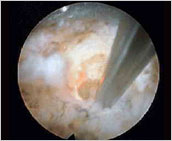

微细钳子

用3mm的微细钳子在内窥视镜下可摘除突出的椎间盘